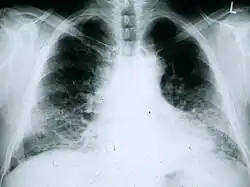

Radiologie

La radiographie du thorax est utile pour le suivi courant des patients atteints de fibrose pulmonaire idiopathique. Une radiographie classique ne permet malheureusement pas d’établir le diagnostic mais peut faire état d’un volume pulmonaire diminué, avec des atteintes interstitielles réticulaires typiques importantes près de la base des poumons[1].